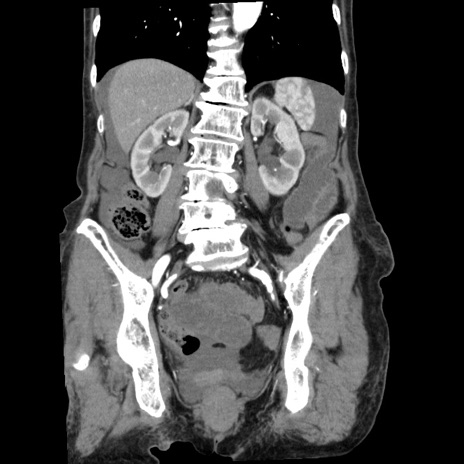

横断像